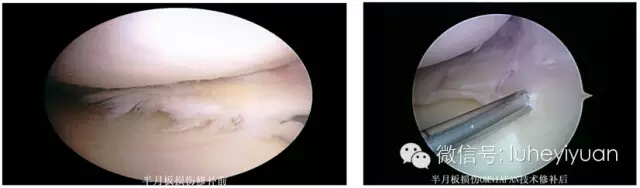

华裔篮球巨星林书豪因半月板损伤遗憾缺席NBA,此前也有很多天赋异禀的球星倒在了半月板伤势的面前。最近首都医科大学附属北京潞河医院骨关节和运动医学科收治了两名前交叉韧带撕裂合并半月板损伤的患者,病情较林书豪更为严重。经过严格的术前检查和准备,骨关节和运动医学科于7月3日成功进行了前交叉韧带重建、OMNISPAN全内缝合修补半月板,填补了该院一项技术空白。

OMNISPAN全内缝合法是国内外关节外科领域最新治疗半月板损伤缝合技术,完全属于全关节内缝合,其具有完全在关节内操作、无需额外的辅助切口、手术时间短、血管神经损伤少、缝合愈合率高等优点。进行前交叉韧带重建术患者的半月板修补缝合术,这样可以保留半月板功能。它是治疗前交叉韧带重建一期半月板修补的理想方法,操作简单、并发症少、疗效确切、治愈率高,值得在临床上推广应用。骨关节和运动医学科成功开展该项新技术标志着该院在关节韧带重建、半月板修复治疗领域又取得了突破性进展,为将来的临床应用提供了更为广泛的平台,为通州区及周边地区患者带来了福音,为医院学科建设增加了一份技术支持。